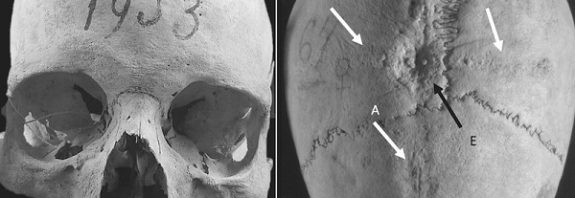

Orta Çağ İtalya’sında Kafatası Ameliyatı Yaptırmak 6. yüzyıldan 8. yüzyıla kadar olan dönemde, İtalya’da bir kadın, kafatasının tepesinde bir delik … Orta Çağ İtalya’sında Kafatası Ameliyatı Yaptırmak okumayı sürdür